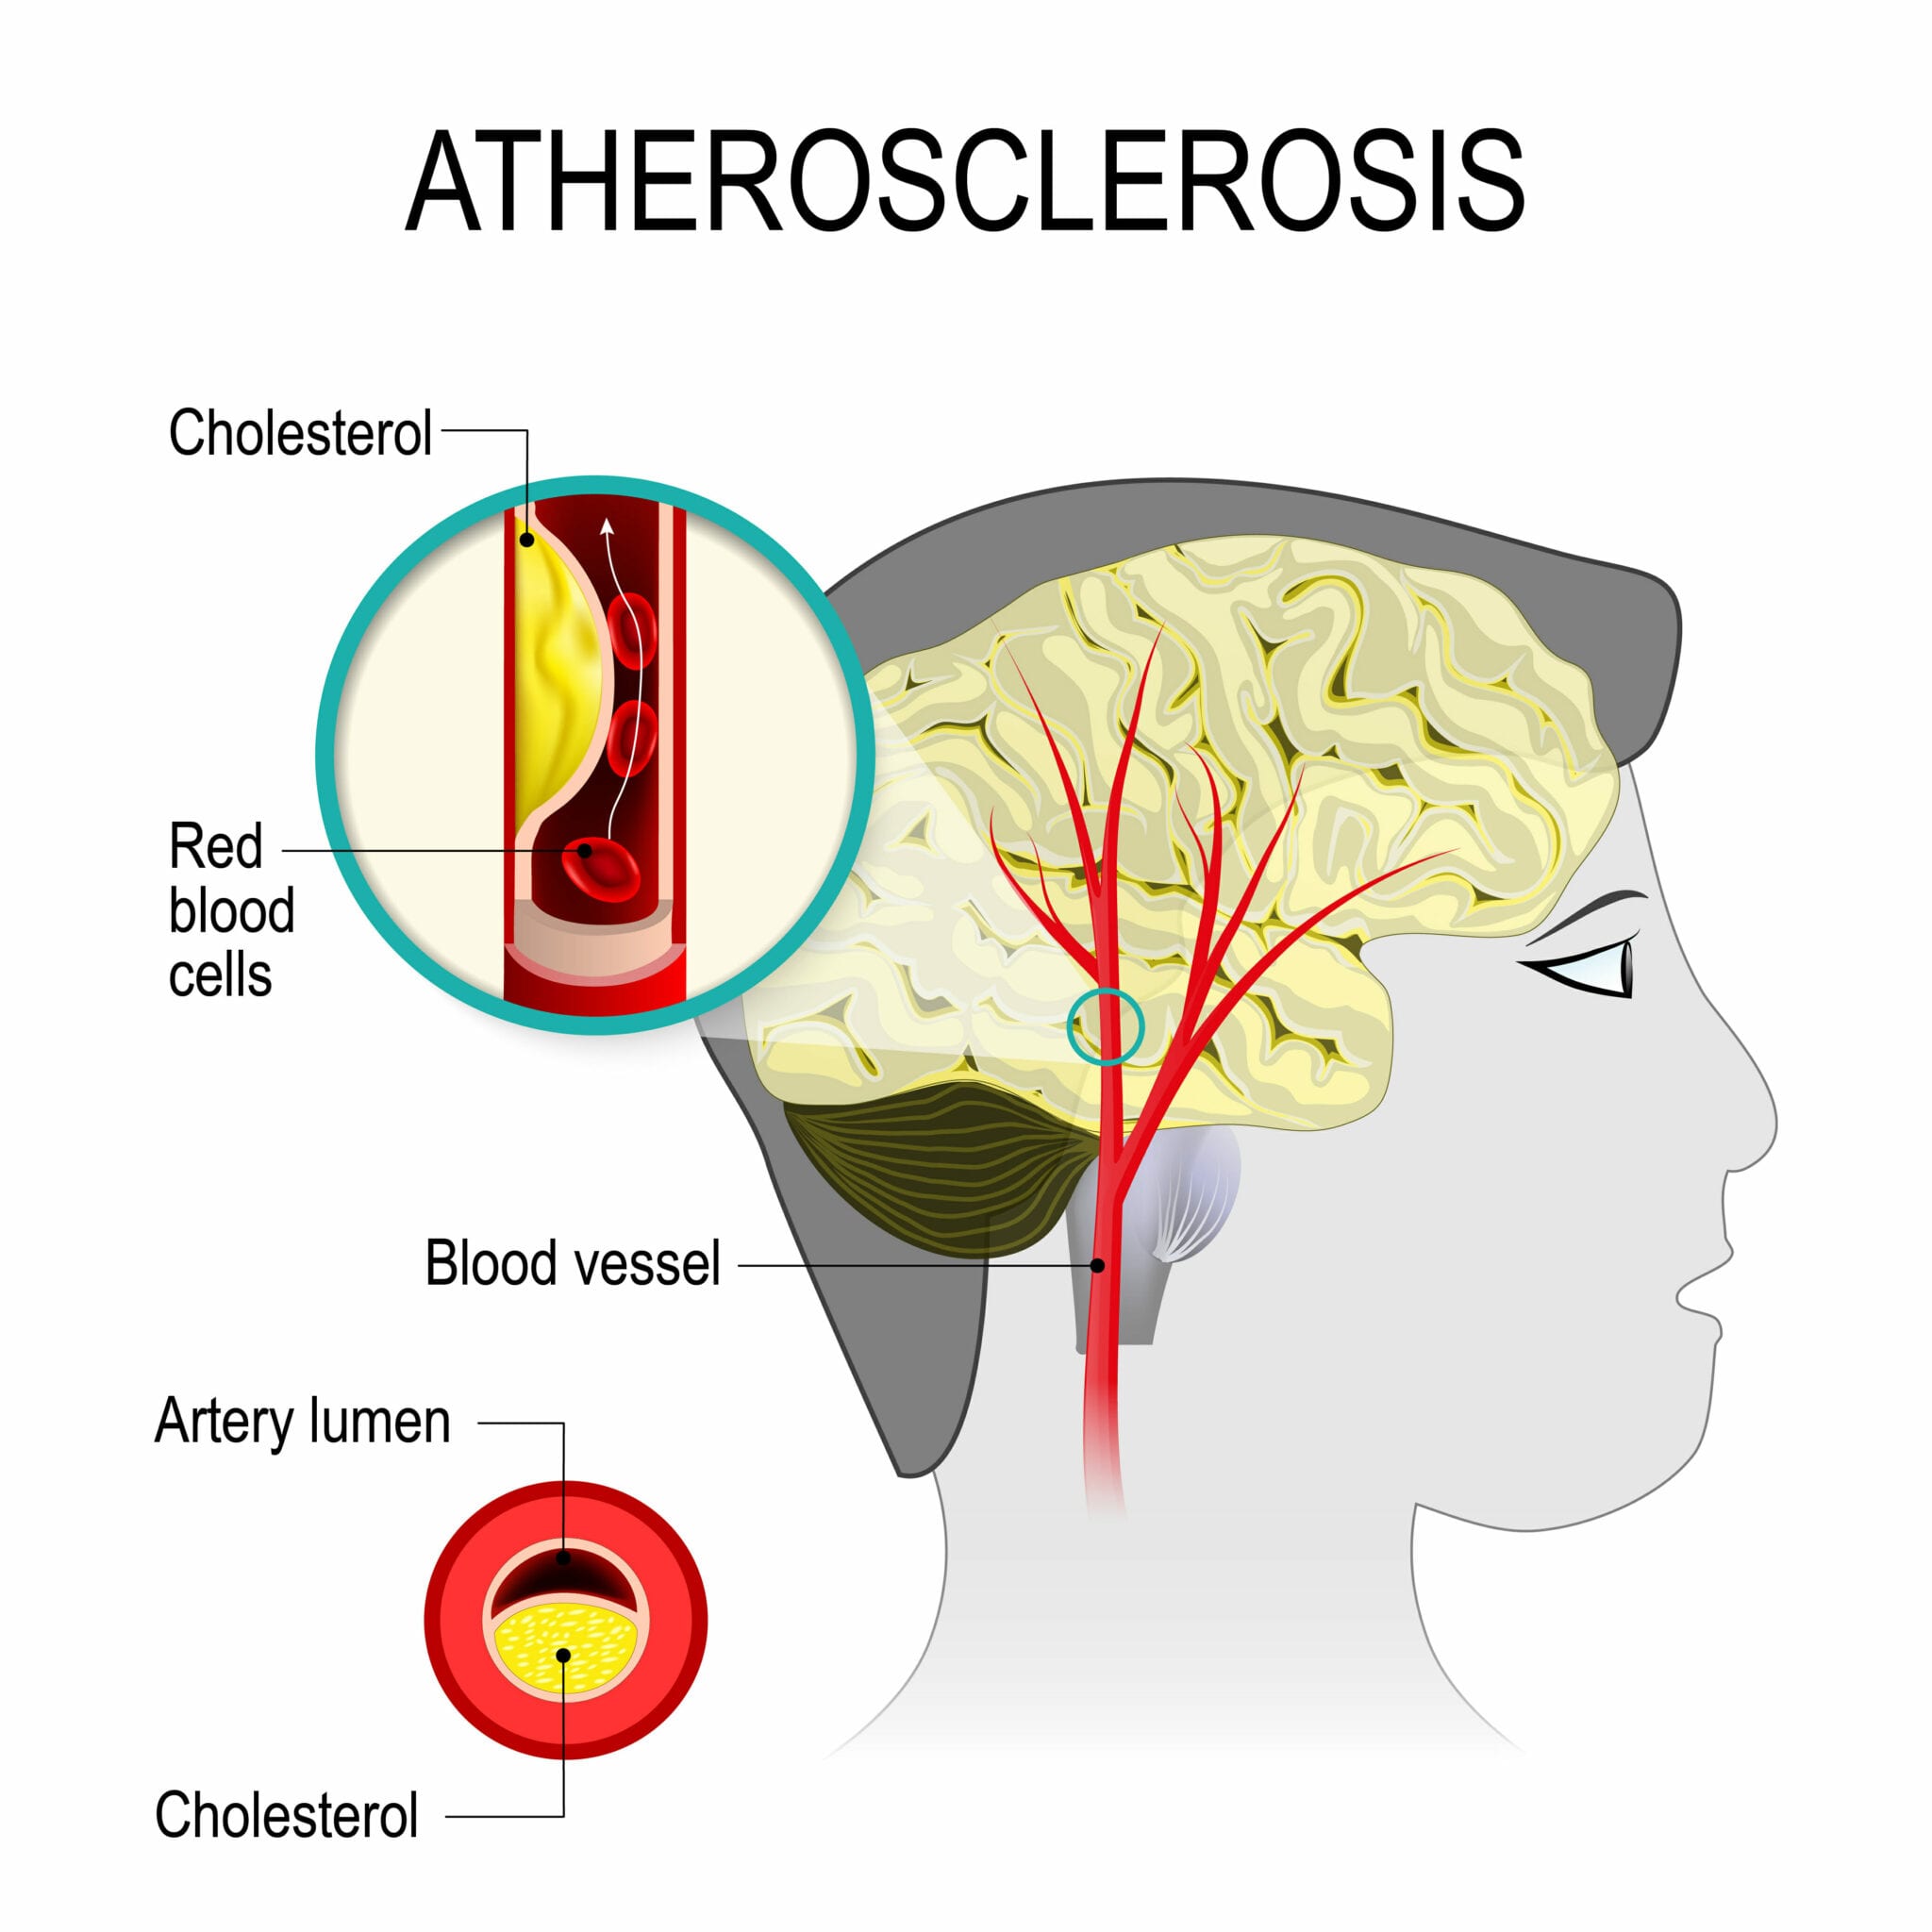

Atherosclerosis | Linus Pauling Institute | Oregon State University

Atherosclerosis | Men’s Health Resource Center

Arteriosclerosis / atherosclerosis – Symptoms and causes – Mayo Clinic

The plaque distribution on middle cerebral artery (MCA) walls. A …

Atherosclerosis and Alzheimer – diseases with a common cause …